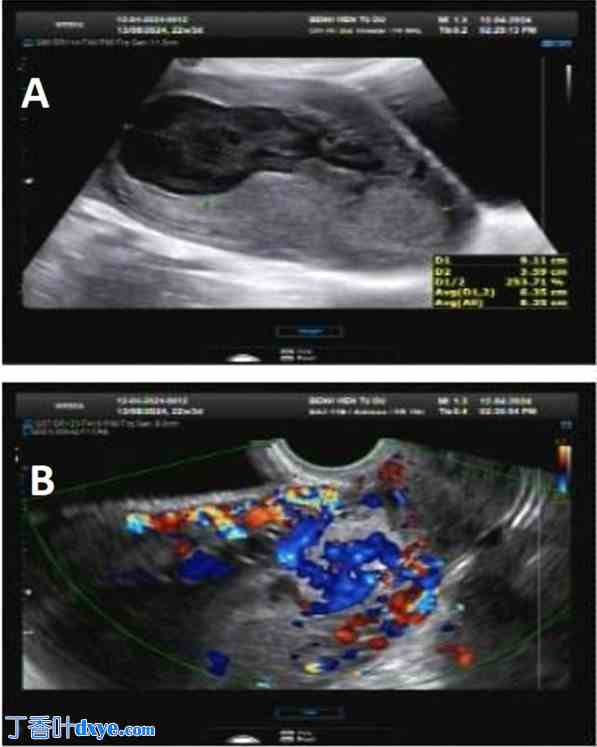

患者每 2 周接受一次超声检查,发现异常血管增生(图 3A-D)。最初,患者还接受了两剂促性腺激素释放激素激动剂 (GnRH-a)。3 个月后,患者因先前剖宫产瘢痕处血管结构异常增生而再次入院。除少量褐色分泌物外,患者无任何症状,血流动力学稳定。β-hCG 水平测量为 14.59 mUI/mL。血清实验室检查结果完全正常。然而,肿块进展迅速。超声扫描显示一个大小为33 × 16 × 29 mm的富血肿块,其“湖”中心最高收缩期峰值速度 (PSV) 为41.4 cm/s,阻力指数 (RI) 为1.0(图4A、B)。先前剖宫产部位的残留子宫肌层厚度较薄。怀疑为动静脉畸形,需与假性动脉瘤鉴别。

图3.

子宫下段前壁靠近先前剖宫产疤痕处(白色箭头)处可见一个无回声的复杂囊性结构,内含多个管状蛇形囊腔。该富血肿块位于剖宫产部位,推测为剖宫产疤痕妊娠。子宫内膜较薄,无宫内或宫外妊娠征象(A-C)。彩色多普勒超声子宫矢状切面显示子宫结构弯曲,动静脉混合血流、颜色混叠和血流倒流,收缩期峰值血流速度增快至40.92 cm/s,阻力指数低至0.27,提示可能存在动静脉畸形(白色圆圈)(D)。